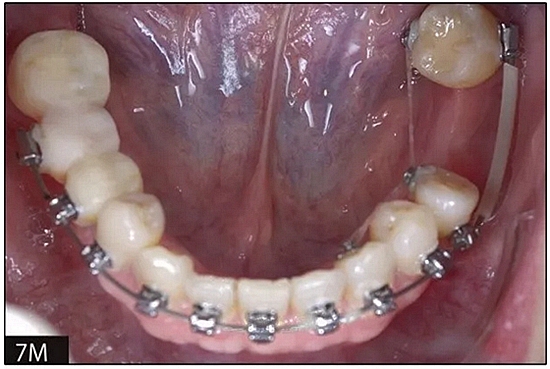

完全固定的Damon Q設(shè)備(加利福尼亞州Glendora的Ormco)與制造商指定的弓絲和附件一起使用。下頜弓,一開始放入0.014英寸的鎳鈦弓絲,5個(gè)月后放入0.014×0.025英寸的鎳鈦弓絲。舌側(cè)扣和鏈圈放置在下頜尖牙和第二前磨牙上以控制扭轉(zhuǎn)。在治療的第7個(gè)月,將下頜弓絲換成0.017× 0.025英寸的β鈦絲。另一個(gè)舌側(cè)扣和鏈圈放置在下頜左側(cè)第三磨牙上以提供近中牽引力(圖9)。在16個(gè)月的治療結(jié)束時(shí),所有的扭轉(zhuǎn)都得到了矯正,缺牙間隙縮小到8 mm(圖8),但由于頰側(cè)骨板的嚴(yán)重吸收,牙槽嵴的寬度仍然很窄(約3 mm)(圖9)。通過正畸移動(dòng)下頜左側(cè)第二前磨牙,在前磨牙之間產(chǎn)生一個(gè)種植部位。在第一和第二前磨牙之間的弓絲上放置一個(gè)推簧,并將舌側(cè)扣和鏈圈放置在第一前磨牙和第三磨牙之間(圖9),在頰側(cè)和舌側(cè)施加力。施力均為輕力,每個(gè)表面上約2盎司(28.3 cN)以控制牙根側(cè)面的吸收。

圖8

圖9